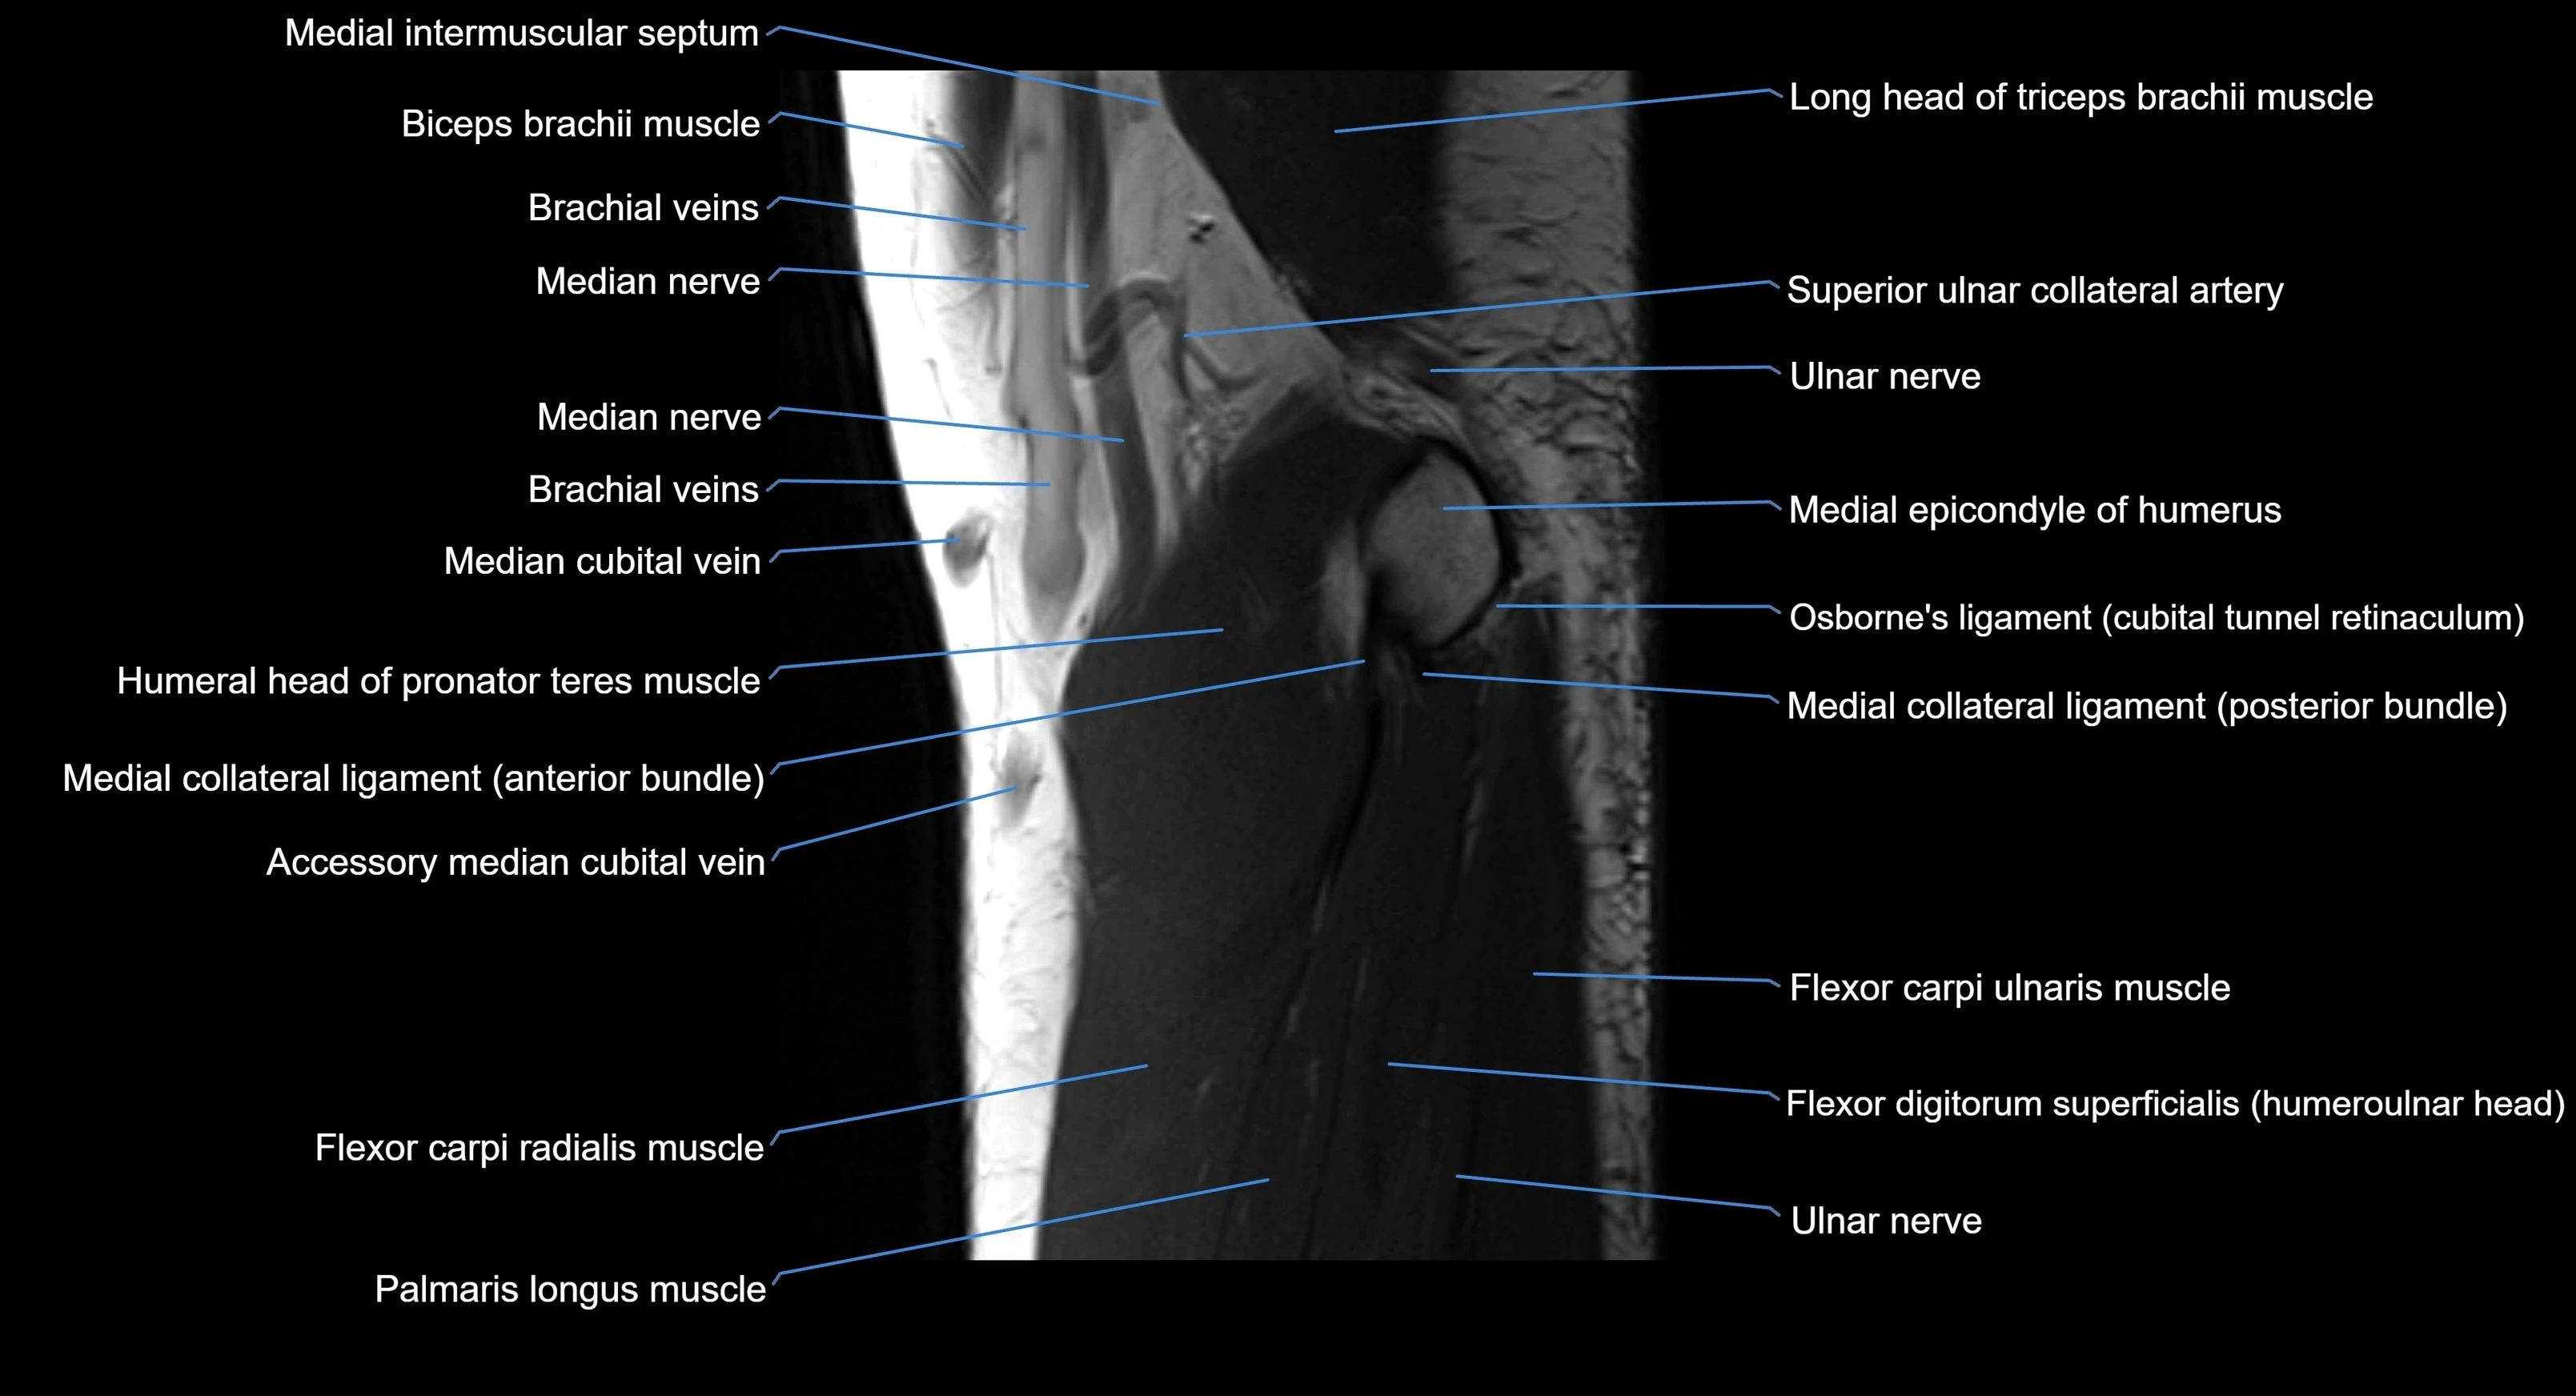

MRI image

image